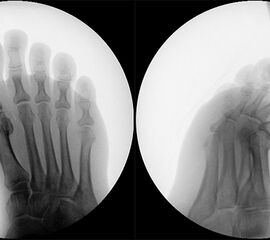

• Röntgen: Fuß belastet in 3 Ebenen.

• Optional MRT und CT bei radiologisch unklaren Verhältnissen.

Zum Lesen der Bildbeschreibung und zur Vollansicht bitte das Bild anklicken (Foto: M. Walther).